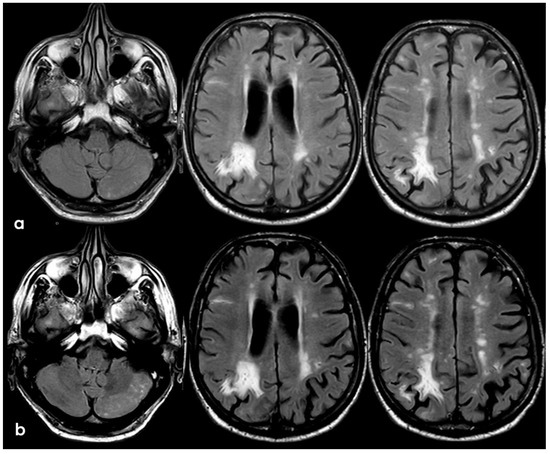

3. May 2014: CAA-Related Inflammation

5. February 2017: First Recurrent CAA-Related Inflammation

7. April 2018: Second Recurrent CAA-Related Inflammation

8. April 2018: Third Recurrent CAA-Related Inflammation